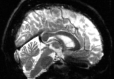

Refer to captionRefer to captionRefer to captioninitializationOptimal TransportRefer to captionRefer to captionRefer to captionOptimal Transport (blurred)Refer to captionRefer to captionRefer to captionMultilevelRefer to captionRefer to captionRefer to captionoptimizedRefer to captionRefer to captionRefer to captionRefer to captionRefer to captionRefer to caption

Figure 6: Example field maps (Subject ID 826353) at initialization (top row) and after optimization with Gauss-Newton (bottom row). The first column uses the proposed optimal transport initialization scheme. The middle column uses the same scheme with an additional Gaussian blur to promote smoothness. The right column uses the coarse-to-fine multilevel initialization scheme from HySCO with five levels, and the final field map is optimized at the original image resolution. The multilevel initialized field map is smooth by construction and further optimized to improve the relative image distance at the full resolution. The optimal transport initialization accurately corrects the distortions but is not smooth in the non-distortion dimensions unless blurred with a Gaussian. After the fine-level optimization all field maps are visually similar.